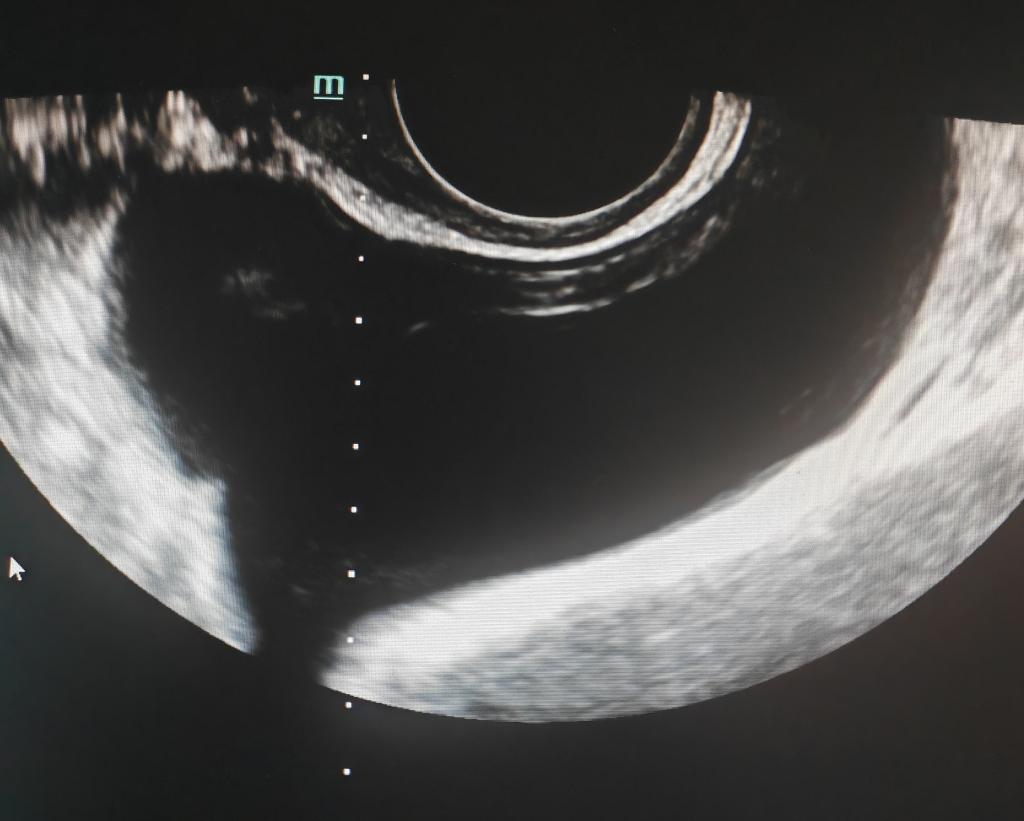

▲术前评估

44岁女性,发现右侧附件囊肿数月,近期出现右脚麻木,既往有附件囊肿腹腔镜手术史,现复发不愿再次手术,于是到我科行穿刺硬化治疗。术前彩超、磁共振检查了解囊肿大小(68.5*43.5mm)、形态及位置毗邻,确定穿刺所需体位以及进针方向、深度,局部消毒后,在超声实时引导下,沿穿刺线精准刺入囊腔,用注射器共抽出90ml液体,蛋白定性试验阳性,冲洗干净后注入硬化剂,超声显示囊腔基本消失,术后盆腔无出血,双脚麻木立刻消失,体表无瘢痕,仅见一针眼。